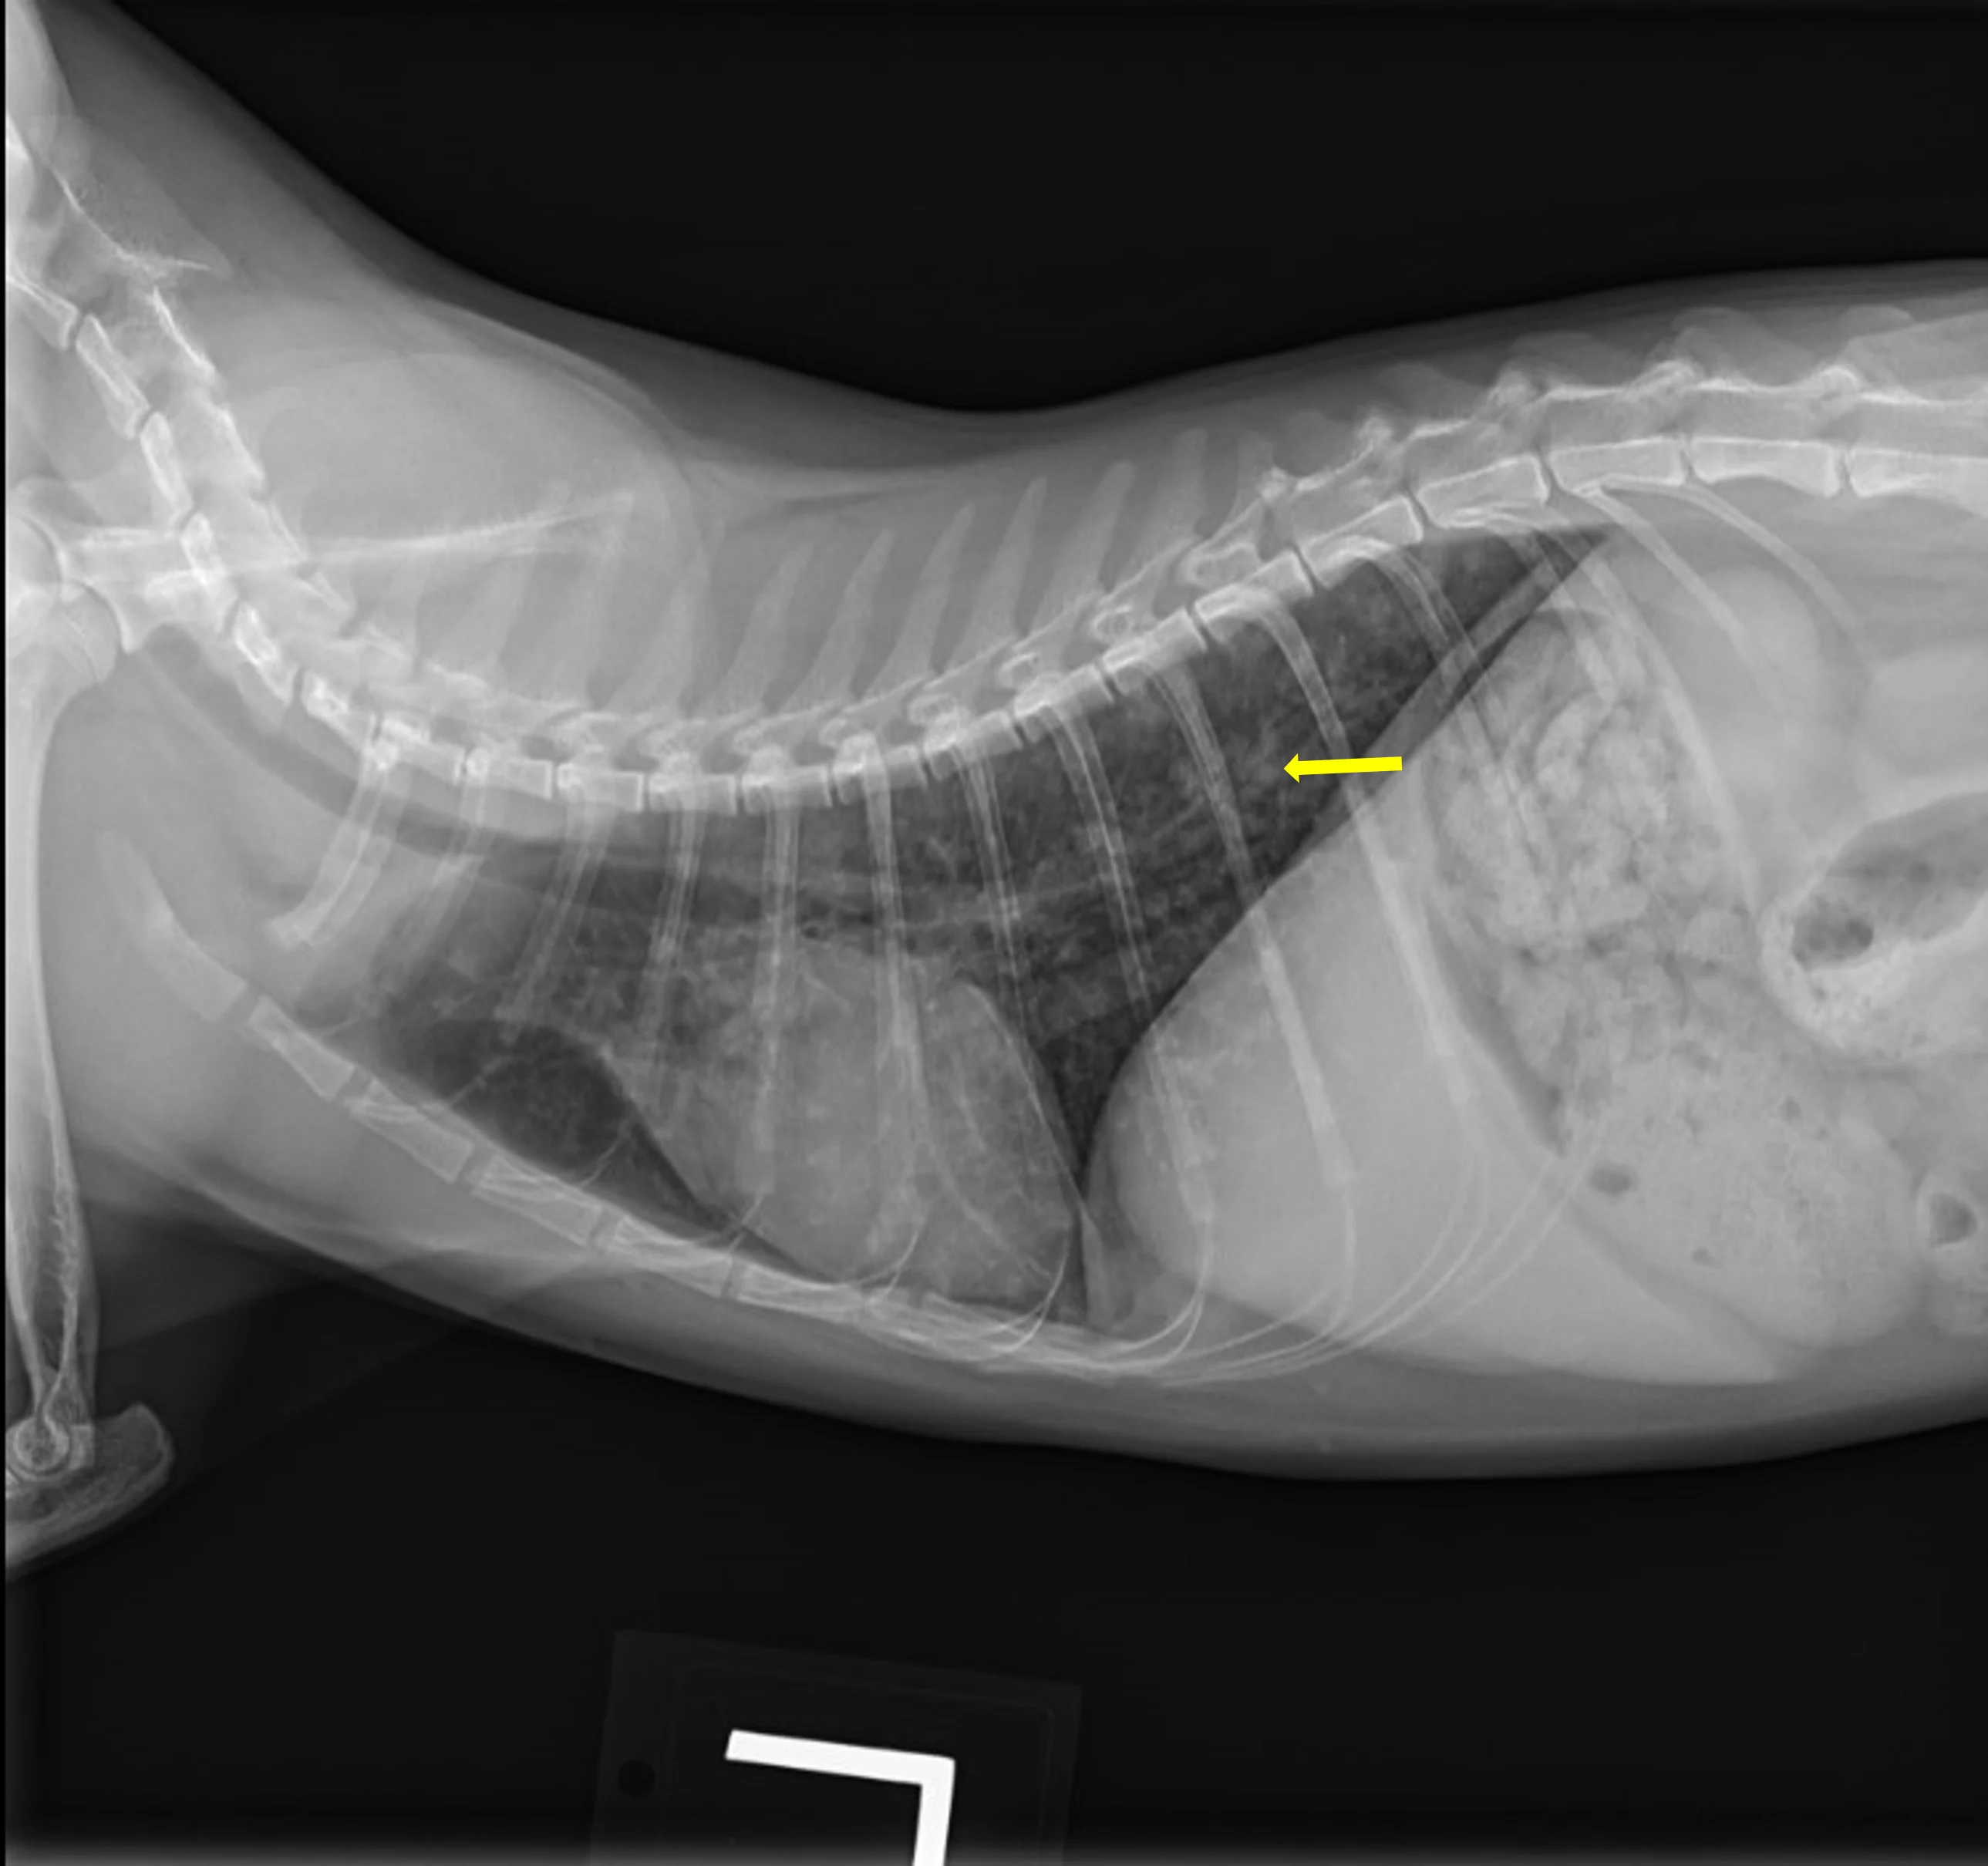

At the 1-month recheck, her weight had increased to 6 lb (3 kg); estimated BCS was 3/9. Physical examination showed a normal respiratory pattern, but increased bronchovesicular sounds were still present bilaterally. No fundic abnormalities were noted. Radiographs indicated subtle improvement of the diffuse nodular pulmonary pattern (Figure 2).

A

FIGURE 2 Left lateral (A), right lateral (B), and ventrodorsal (C) thoracic radiographs 1 month after initiation of itraconazole. Subtle improvement of the diffuse nodular pulmonary pattern can be seen.